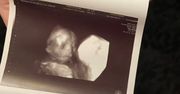

Niesamowite zdjęcia USG. Nawet lekarze byli zaskoczeni

Badanie USG to zwykle jeden z najbardziej wyczekiwanych momentów w czasie ciąży. Jesteśmy ciekawi, jak będzie wyglądać nasze dziecko, jaki będzie miało kształt nosa czy uszu. Czasem jednak zamiast radości, zdjęcie USG może stać się powodem niepokoju i stresu. Tak było w przypadku Jade Boyland z Somerset w południowo-zachodniej Anglii, która na swoim pierwszym badaniu USG ujrzała twarz swojego dziecka. Była przerażona, ponieważ zobaczyła zarys zgarbionego malucha, z wielkimi oczami i wydłużonymi palcami, które przypominały szpony. Jade przyznała, że gdy pierwszy raz zobaczyła twarz swojego malucha, nazwała "demonicznym dzieckiem". Początkowo żartowała z tego, jednak wraz z biegiem ciąży coraz bardziej przejmowała się kwestią wyglądu córki po porodzie. Niepokój jednak okazał się zbyteczny, ponieważ urodziła piękną, zdrową córeczkę, która obecnie ma 9 lat. Po "demonicznym wyglądzie" nie ma żadnego śladu. Jednak, jak twierdzi mama, córka ma "demoniczny charakter" i żartuje, że wiedziała to od pierwszego badania. Tak obecnie wygląda Lydia